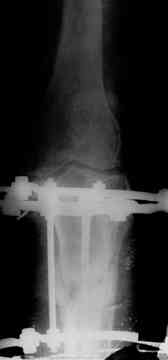

23- августа было сообщено о больной 68лет, с ложным суставом в/з б/берцовой кости. Представляем промежуточной результат операции. Коррекция варусной деформации на аппарате Илизарова постепенной клиновидной дистракцией, больная самостоятельно ходить, ногу нагружает полностью, болей нет, движение в коленном суставе улучшилось. Дальше что делать? Продолжать ЧКДО или перейти на другой вид фиксации?

Продолжать "ЧКДО", т.к. до сих пор не устранена антекурвация , да и некоторая гиперкоррекция варуса не необходима!!!